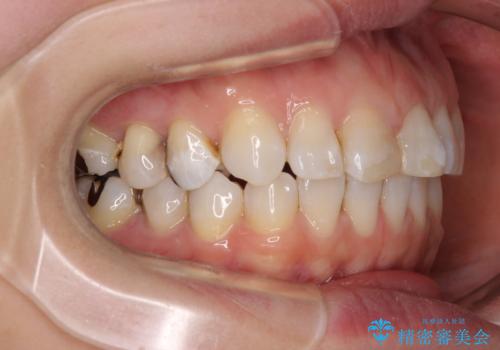

- 前歯のデコボコを治したいとのことで来院された患者様です。

上下顎ともに歯列全体の後方移動とIPR(歯と歯の間を削る)によってデコボコが解消するように設計し、インビザラインにより治療を行うこととしました。

しっかりと装着時間を守ってくださったのですが、途中妊娠にともなう悪阻や出産といったイベントがあり、予定よりも治療期間が長くなりました。